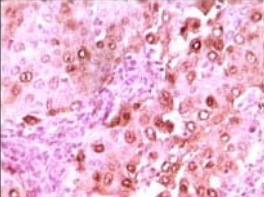

S100A6 Mouse Monoclonal antibody[7D11A]

IHC    1/200 - 1/1000